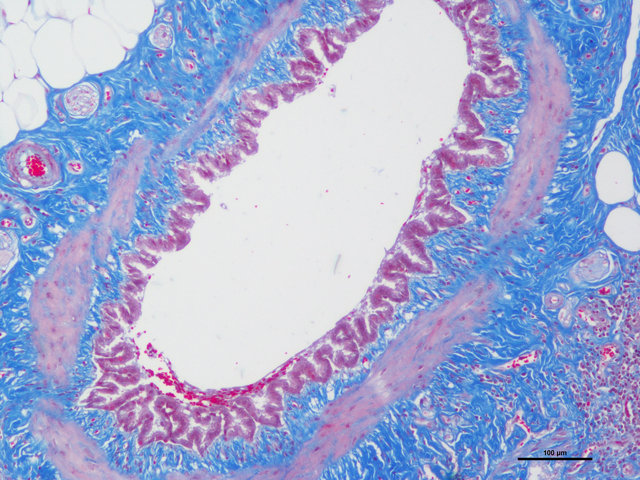

Masson染色

Masson氏染色时胶原纤维呈蓝色(被苯胺蓝所染)或绿色(被亮绿所染),肌纤维呈红色(被酸性品红和丽春红所染),这与阴离子染料分子的大小和组织的渗透性有关。如已固定的组织用一系列阴离子水溶性染料先后或混合染色,则可发现红细胞被 最小分子的阴离子染料着染,肌纤维与胞质被中等大小的阴离子染料着染,而胶原纤维则被大分子的阴离子染料着染。由此 说明了红细胞对阴离子染料的渗透性最小,肌纤维与胞质次之,而胶原纤维具有最大的渗透性。根据组织不同的渗透性能, 选择分子大小不同的阴离子染料进行染色,便可把不同组织成分显示出来。

实验结果:

胶原纤维呈蓝色;胞质、肌纤维、红细胞呈红色;胞核黑蓝色。

样片参考: